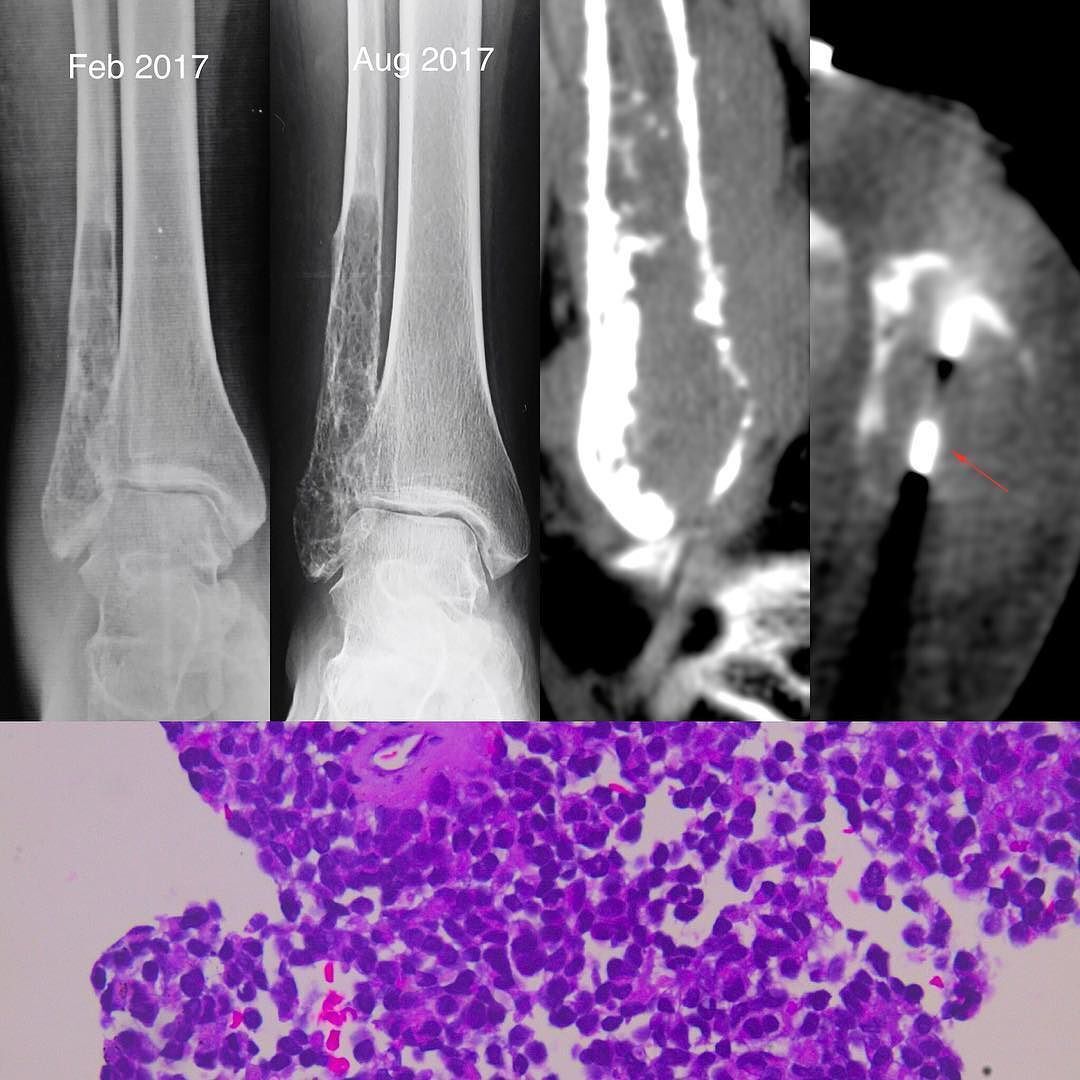

Imaging Tests: For example, CT scans, MRIs, and PET scans help doctors visualize the size and location of the mass and whether it has spread elsewhere in the body.

Biopsy: There are several types (needle biopsy/surgical biopsy) depending on the location/size of the tumor. In this type of biopsy, a piece is extracted for examination under a microscope to confirm the presence of malignant cells, such as sarcoma. The type of biopsy depends on where in the body the tumor is found, as well as its size.